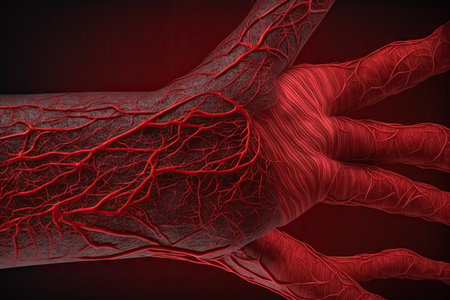

red muscle fibers of arm on background of microblood vessels, created with generative ai

A detailed close-up image of a human hand displaying realistic red veins and intricate skin texture, ideal for medical and artistic use.

Colorful depiction showcases a complex arrangement of muscle fiber patterns in various red hues, emphasizing the detailed structures and textures